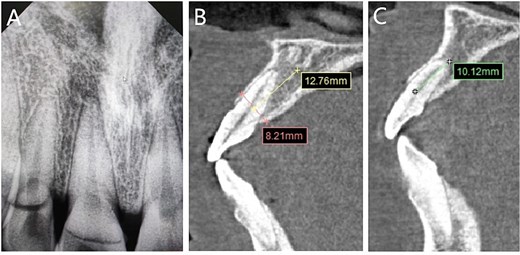

Imaging examinations

Preoperative dental film revealed 11 and 12 crown-root fracture (Fig. 2A), while results from cone beam computed tomography (CBCT) showed that the lingual fracture line of 11 tooth was located under the alveolar bone, the buccal bone was thin (<1 mm), and the height of alveolar bone was sufficient (Fig. 2B). The lingual side of 12 tooth crown was located at the top of the alveolar crest, with a root length of about 10 mm. No obvious periapical shadow was found (Fig. 2C).

Imaging examinations. (A) The dental film; (B) 11 tooth position in CBCT images; (C) 12 tooth position in CBCT images.